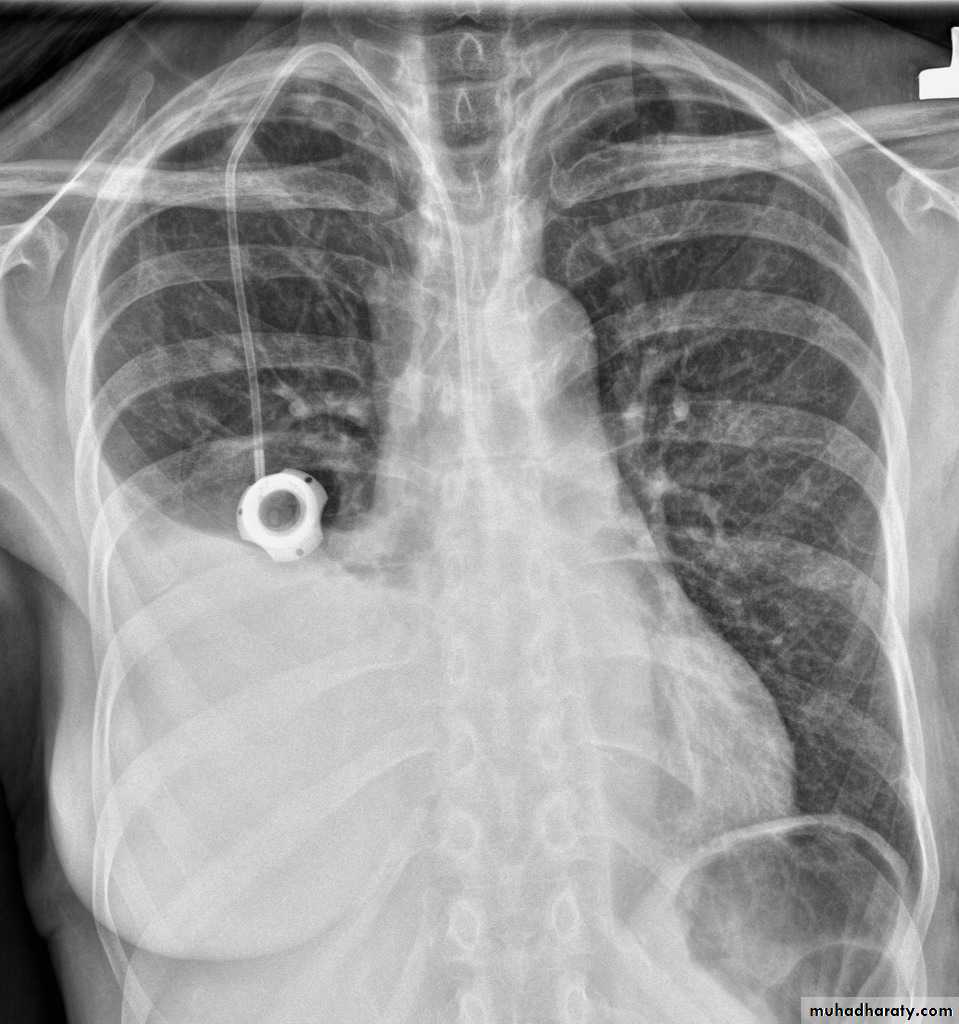

History: dyspnea, weight loss, dehydration with poor immunity

History; too shy to take of his shirt in the pool!